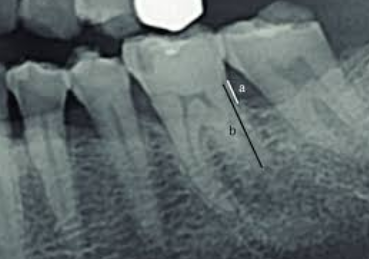

Elongation

What it looks like:

Teeth appear long and stretched.

Cause:

Insufficient vertical angulation.

Fix:

Increase vertical angulation.

Foreshortening

Teeth appear short and stubby.

Excessive vertical angulation.

Reduce vertical angulation.